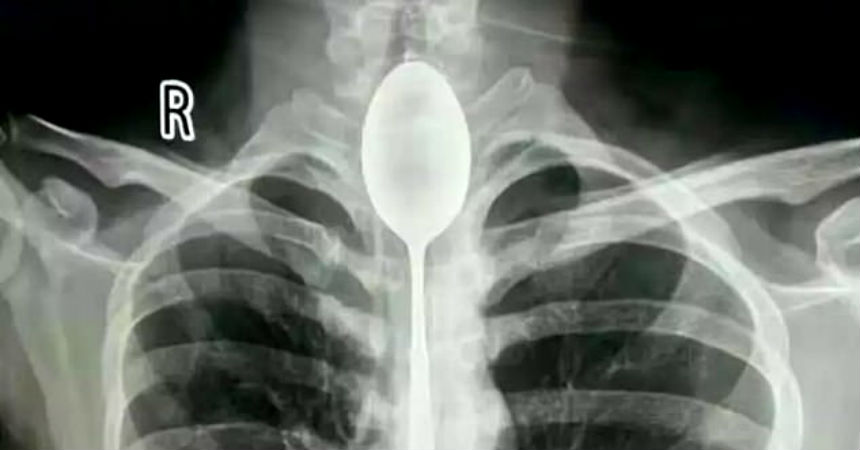

Es lo que ocurrió con un hombre de 26 años que llegó al Hospital General de Xinjiang Meikuang, en China, con una cuchara de 20 centímetros atorada en el esófago. Lo más curioso es que el objeto lo tenía alojado hace un año en su interior, según señala Daily Mail.

"Quedé impactado. Nunca he tenido algo así", dijo Yu Xiwu uno de los médicos que trató al paciente, el cual ya tenía complicaciones en su cuerpo lo que le había provocado una infección en esófago.

Según reconoció el paciente, de apellido Zhang, todo se debió a una apuesta que hizo con unos amigos, donde aseguró que era capaz de tragarse una cuchara. El hombre cumplió su palabra y lo hizo. El problema es que luego no pudo sacársela y anduvo un año con el objeto dentro de su cuerpo.

El hombre señaló que no había acudido antes al hospital porque en ningún momento le había molestado para hablar o comer. Sin embargo, un día recibió un golpe en el pecho lo que le provocó complicaciones derivadas a la cuchara que tenía en esófago.

Afortunadamente los médicos pudieron extraer la cuchara y el hombre se recupera satisfactoriamente.